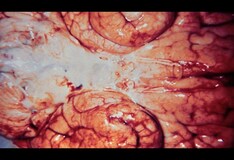

There have been numerous reports linking VZV vasculopathy and stroke syndrome after zoster attacks since the 1970s, the authors write, and VZV is the only recognized human virus able to replicate in cerebral arteries. "It is hypothesized to spread along the nerve fibers to the blood vessels, where it induces further inflammatory and thrombotic responses," Dr. Kang and colleagues note.

VZV vasculopathy can affect both the large and small vessels. In large-vessel VZV vasculopathy, vessels are damaged by inflammation induced by the virus, which can result in stroke. Small-vessel VZV vasculopathy, in contrast, can manifest as nonspecific symptoms including fever, headache, seizures, weakness, consciousness disturbances, and cognitive impairments, known as small-vessel encephalitis.